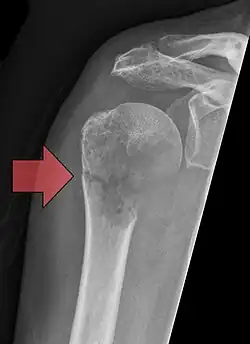

- Aufnahmen pathologischer Frakturen

-

Pathologische Fraktur des Oberarmknochens bei einer Metastase eines Nierenzellkarzinoms -

Pathologische Fraktur des linken Oberarms bei Knochenmetastase einer Patientin mit Brustkrebs -

Ganzkörperknochenszintigramm mit 99mTc-HDP der Patientin mit der Oberarmfraktur aufgrund einer Brustkrebsmetastase